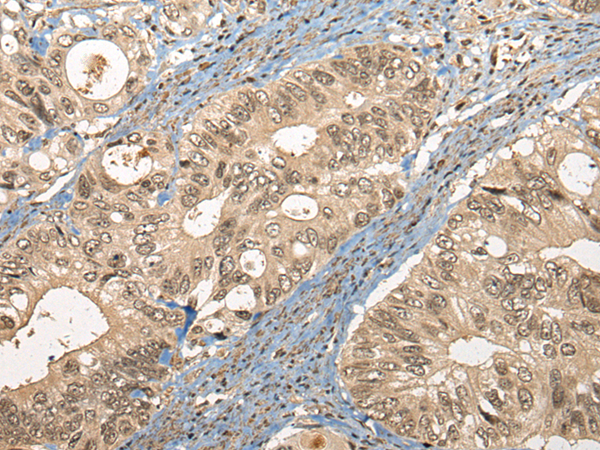

ELISA, IHC |

IHC positive control: |

Human liver cancer and human colorectal cancer |

IHC Recommend dilution: |

30-150 |